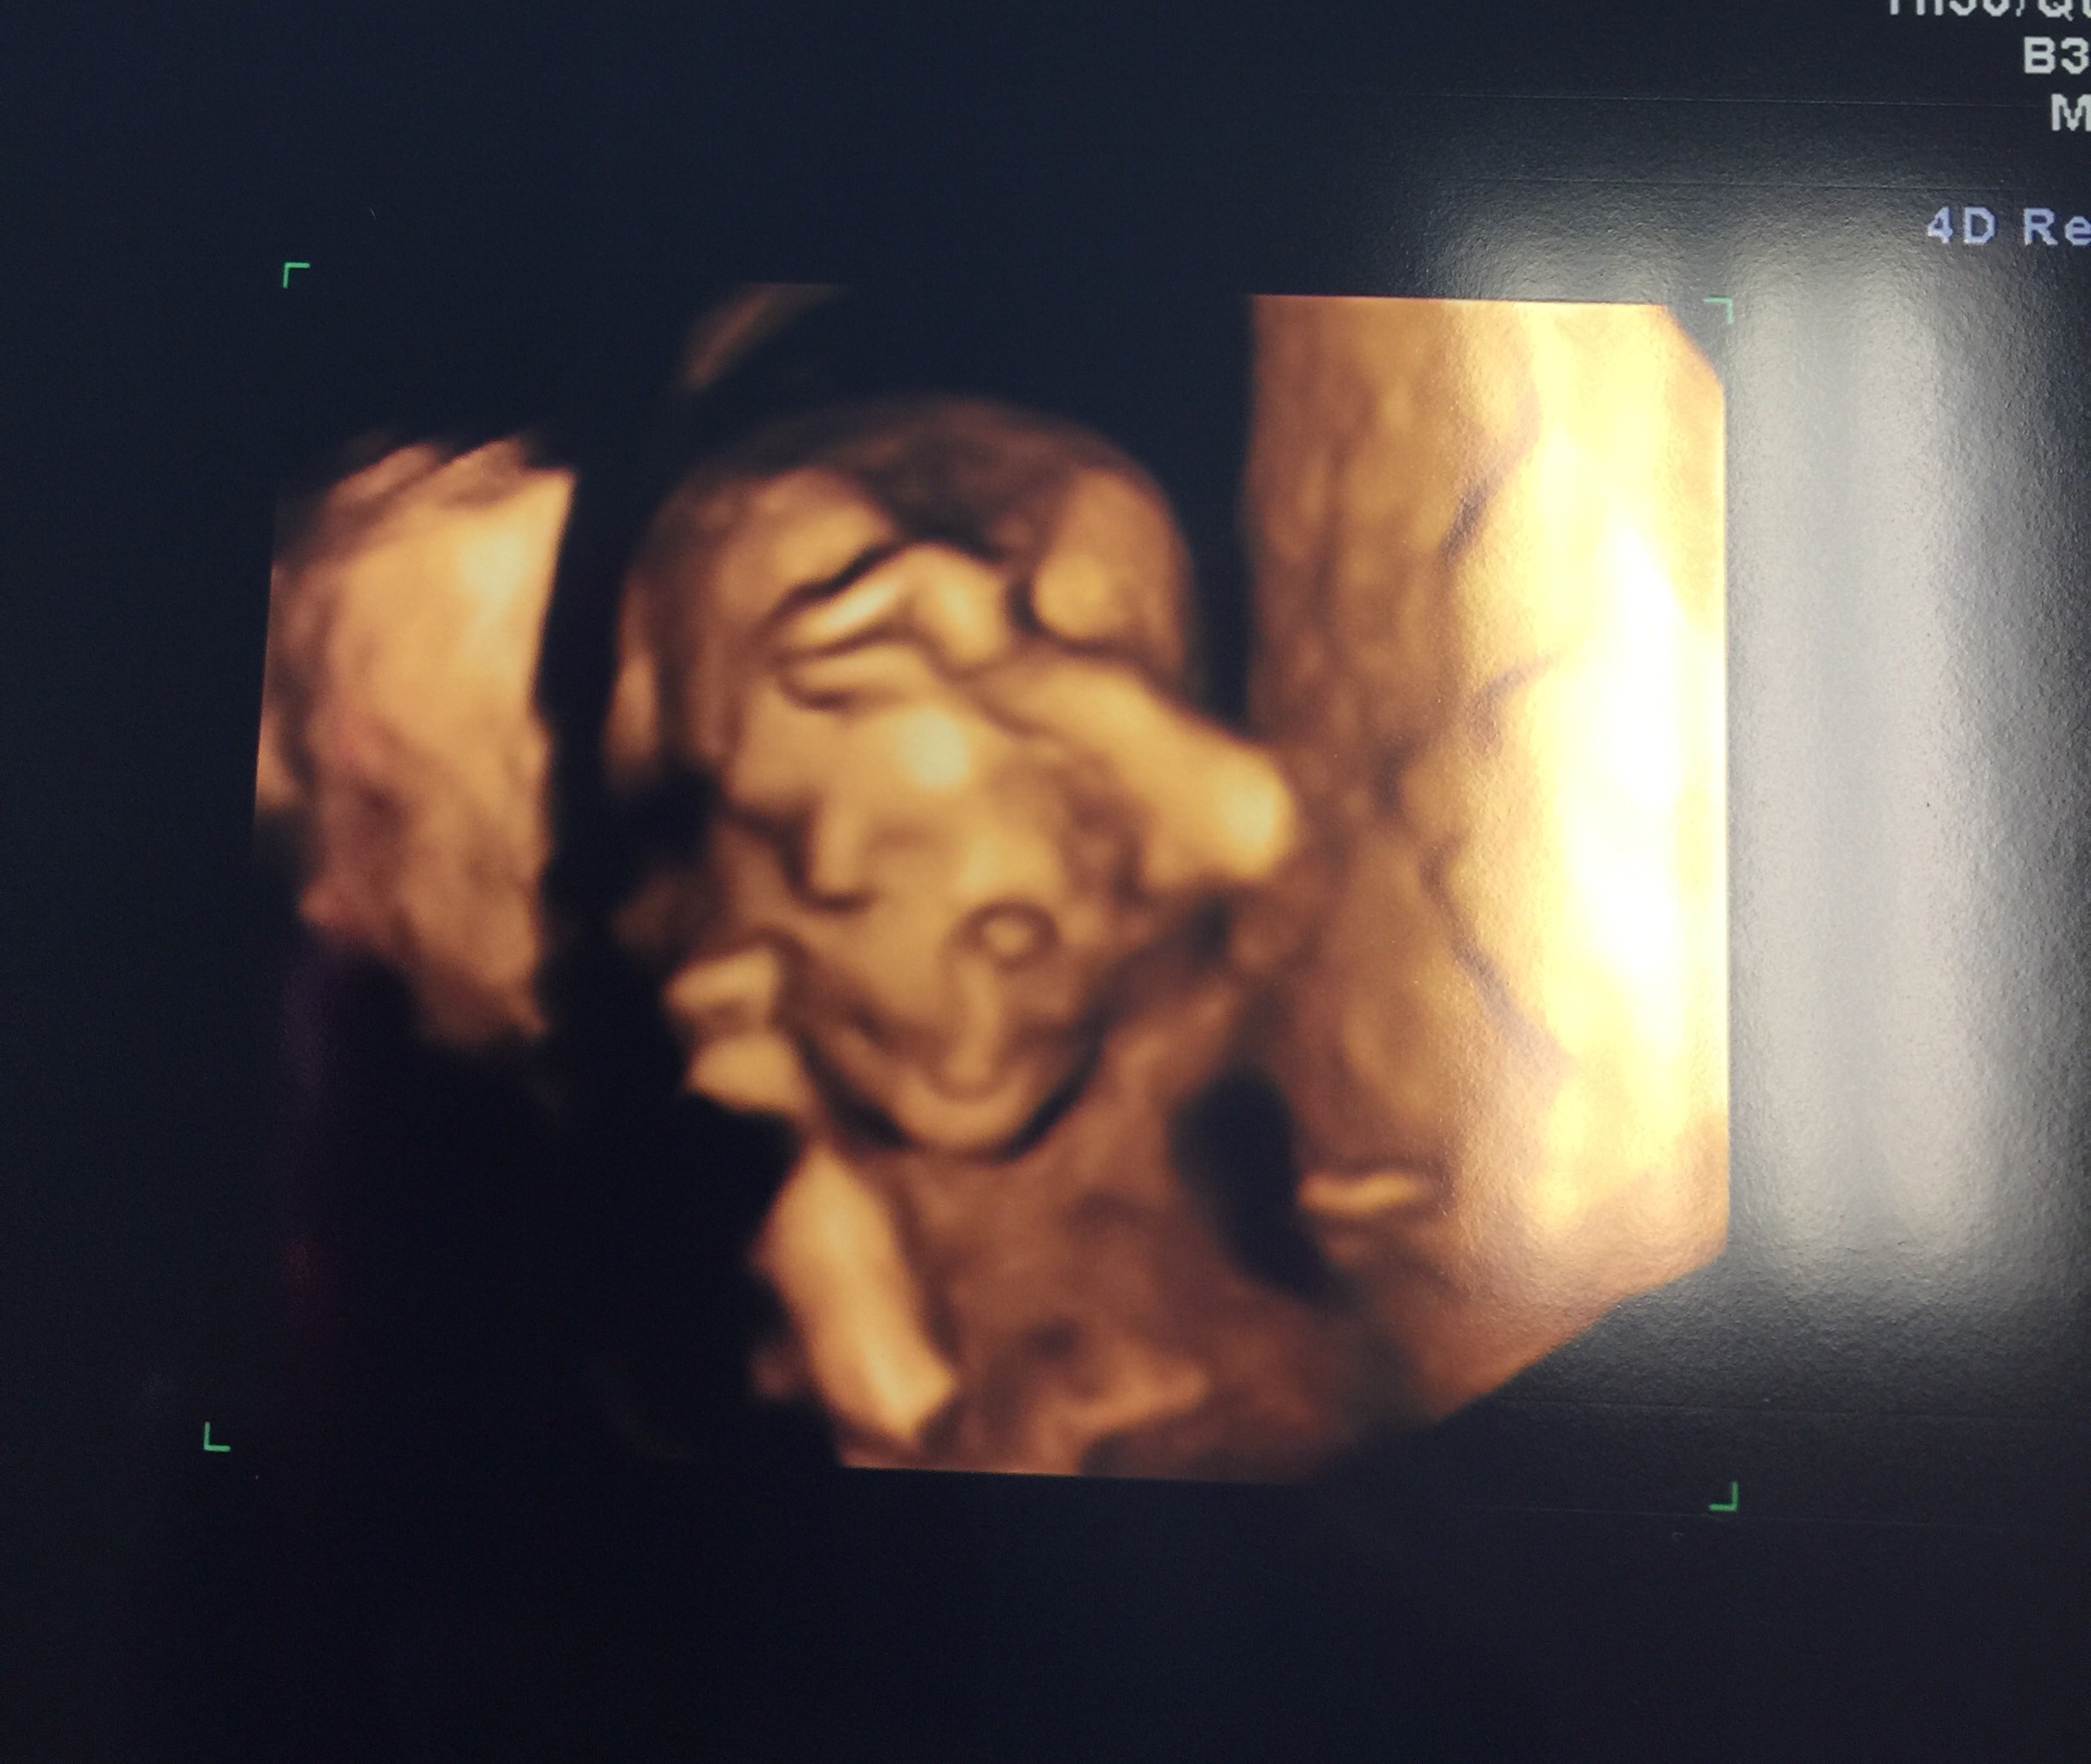

11 weeks and 2 days. This appointment was with my high risk specialist, I hope her nub theory guess was right :x so in love & super happy we got a 3d/4d.